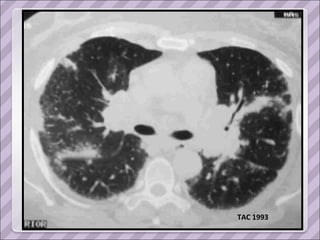

TAC 1993

APP Sarcoidosis torácica  (1993, dx por biopsia ganglionar del mediastino. Estadio II) Compromiso cutáneo (eritema nodoso recurrente y refractario en MMII), ocular (uveítis) y del SNP ( mononeuropatía múltiple). Tratamiento prolongado con corticoides y azatioprina.  Cushing exógeno Diabetes inducida por esteroides Serología positiva para Hepatitis C en 2006